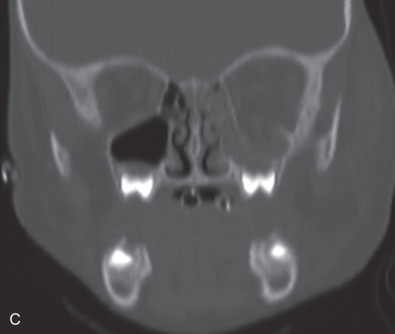

Pediatric facial fractures are relatively uncommon due to the aforementioned bone elasticity, cancellous composition, and higher cranium-to-face ratio. Within pediatric facial fractures, orbital fractures have a wide reported incidence, ranging from 3% to 45% of all facial fractures. Grunwaldt et al. demonstrated that the orbital fracture was the most common facial fracture ( Fig. 2.3.3 ) in all age groups (0–5 years, 6–12 years, 13–18 years). This differs from prior work evaluating the epidemiology of pediatric facial fractures. However, Grunwaldt et al. utilized emergency department-based assessment at a level one trauma children’s hospital, eliminating an inherent selection bias of individual surgeons, consulting department, and hospital admissions.